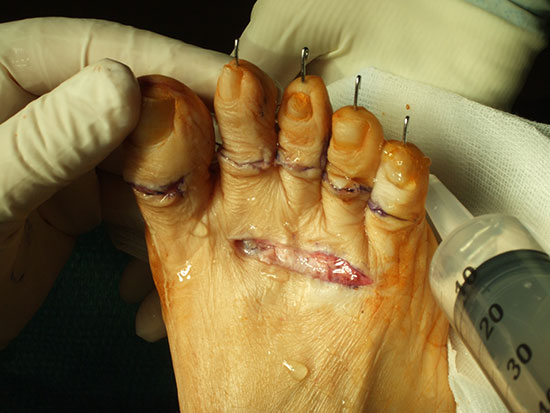

Einbau eines Swanson Spacers

Abbildung 8

Die Nachbehandlung erfolgt unter Vollbelastung im Verbandsschuh für 6 Wochen. Neben den o.g. allgemeinen Komplikationen treten Prothesenbrüche, Silikonabrieb mit Reizsynovialitiden und Osteolysen, Fehlstellungen der Großzehe, Transfermetatarsalgien und Ankylosierungen auf.